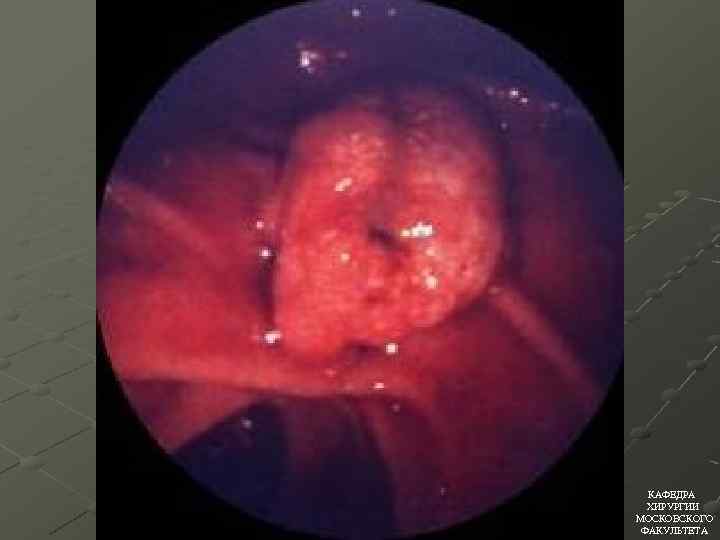

ЭНДОСКОПИЧЕСКОЕ ЛЕЧЕНИЕ ОСТРОГО ОТЕЧНОГО ПАНКРЕАТИТА Эндоскопическая папилосфинктеротомия Эндоскопическое стентирование ЭРХПГ КАФЕДРА ХИРУРГИИ МОСКОВСКОГО ФАКУЛЬТЕТА

ЭНДОСКОПИЧЕСКОЕ ЛЕЧЕНИЕ ОСТРОГО ОТЕЧНОГО ПАНКРЕАТИТА Эндоскопическая папилосфинктеротомия Эндоскопическое стентирование ЭРХПГ КАФЕДРА ХИРУРГИИ МОСКОВСКОГО ФАКУЛЬТЕТА